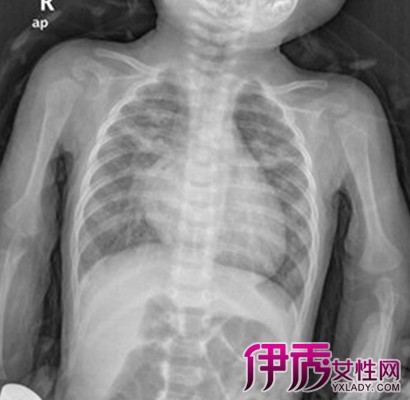

心电图有左房或左室肥厚提示肺动脉高压可能是心源性的,X线胸片显示大的肺静脉血流再分布或Kerley’s B线反映肺静脉高压,肺血增多主要发生于左向右分流性心脏病;超声心动图能够准确地诊断某些心脏病变引起的肺动脉高压,肺功能测定能帮助鉴别阻塞性或限制性肺疾病,血气分析可分清是否缺氧性肺动脉高压,放射性核素可显示肺段及其以上的血栓栓塞性肺动脉高压。